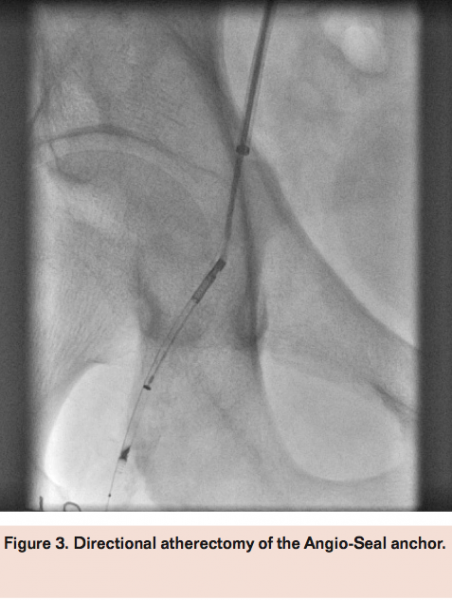

Access was obtained in the left femoral artery with a 7 Fr sheath. Angiography of the right external iliac artery with runoff demonstrated a hazy thrombotic 20 mm subtotal occlusion of the right common femoral artery at the site of previous Angio-Seal device deployment with filling of the distal common femoral artery via microchannels (Figure 2). A Grand Slam wire (Abbott Vascular) was advanced across the lesion into the distal popliteal artery and a Spider 6.0 mm distal embolic protection device (Covidien) was deployed in the popliteal artery. Directional atherectomy with a TurboHawk LSM device (Covidien) was performed (Figure 3) with multiple cuts to eliminate the residual Angio-Seal anchor and collecting some atheroma (Figure 4). The filter was retrieved successfully, which also revealed a moderate amount of macro debris (Figure 4). Final angiogram after adjunctive balloon angioplasty demonstrated good angiographic result with brisk flow through the common femoral artery and minimal residual luminal irregularities (Figure 5).